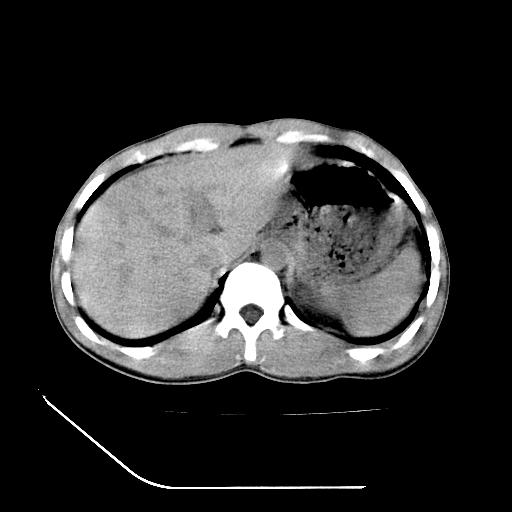

顺便请各位老师认真看看7号片

各位老师觉得胆囊是不是有点积血。我在原始片看胆囊密度不均,似有小液平面

再有就是支持楼主,胆囊7日片比5日片不仅增大许多,靠后下更见液液分层,应该是有积血。

尽管上诉资料说的是b超,但其原理也同样使用于本例病人。12-05片胆囊没有问题,12-07却有类似于出血的高密度,不能 不说是非常奇怪和匪夷所思的现象。特意摘录出来与大家共勉,至少我们在诊断胆囊结石或出血的时候应该划过这样的印象。